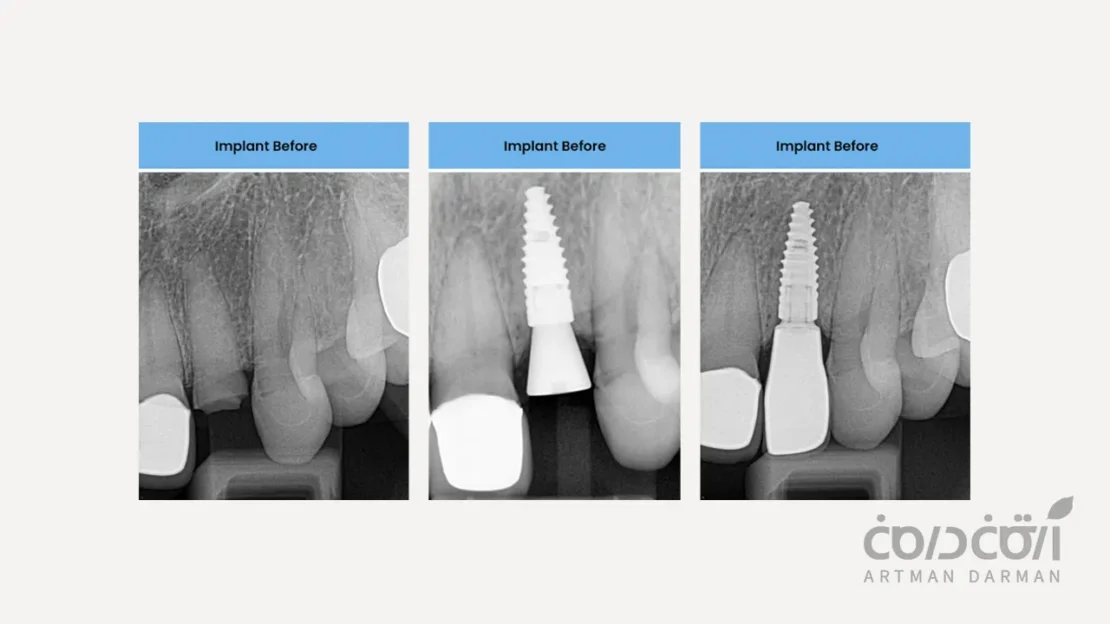

در مقایسه ایمپلنت با دندان واقعی، این مهم ترین شباهت عملکردی است. ایمپلنت دندان مستقیماً در استخوان فک کاشته شده و از طریق فرآیند یکپارچگی استخوانی (Osseointegration) به جزئی ثابت از بدن شما تبدیل می شود.

اما واقعیت ایمپلنت دندان چیز دیگری است (یک اتصال مستقیم و بدون واسطه به استخوان)

در مقایسه ایمپلنت با دندان واقعی، باید بدانیم که ایمپلنت ها فاقد لیگامان پریودنتال هستند. ایمپلنت از طریق فرآیند اوسئواینتگریشن، به صورت مستقیم و کاملاً صلب به استخوان جوش می خورد. این اتصال، که به آن «آنکیلوز فانکشنال» می گویند، هیچ گونه انعطاف پذیری یا حرکت ریزی ندارد. این فقدان PDL، منجر به تفاوت های زیر می شود: